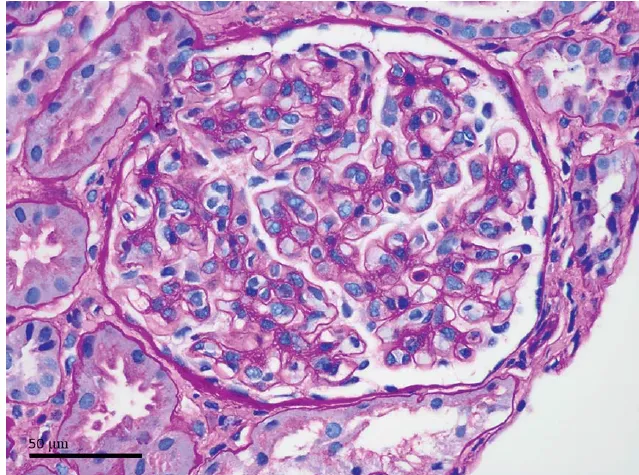

* Hipercalcemia em DRC com perfil PTH-independente.

* 1,25(OH)₂D elevada sugere produção extra-renal por 1α-hidroxilase de macrófagos.

* ECA elevada e PET “quente” próximo à prótese apoiam granulomatose.

• Adjuvante (PMMA) atua como gatilho imune → granulomas ativam 1α-hidroxilase → ↑ calcitriol → ↑ absorção de cálcio e hipercalcemia.

• DRC reduz depuração e amortece compensações, agravando o desbalanço.